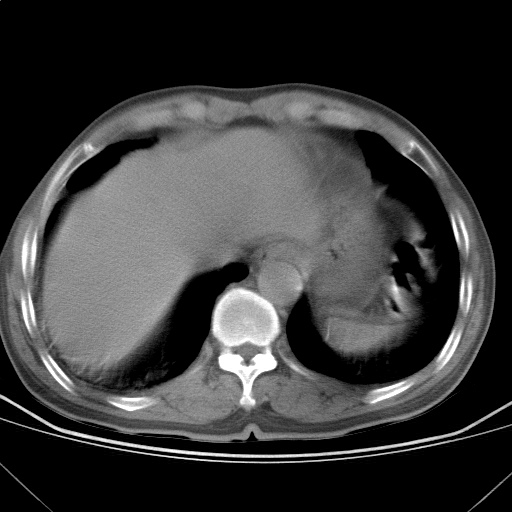

以下是引用随光逐影在2009-5-1 13:53:00的发言:[br]考虑为:1)两肺血行播散型肺结核;2)右肺下叶炎症感染。3)右侧胸膜增厚。